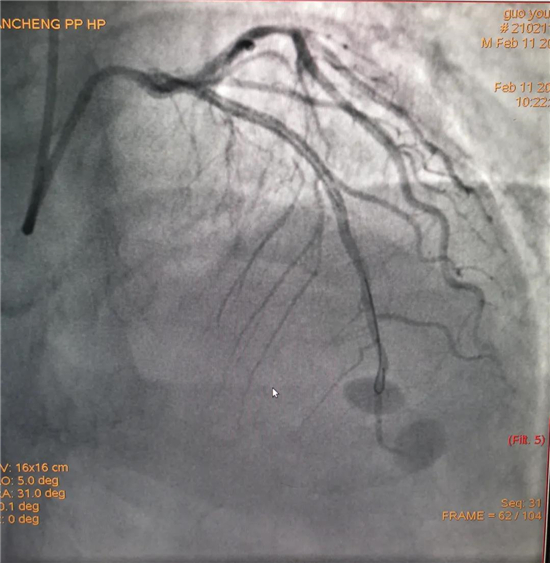

除夕,郭先生無明顯誘因突發(fā)胸痛,120急救人員到達(dá)現(xiàn)場,心電圖顯示:竇性心律完全性束支傳導(dǎo)阻滯。信息立刻發(fā)送到胸痛中心介入微信群中,心內(nèi)科值班醫(yī)生初步診斷為急性廣泛前壁心肌梗死,必須盡快進(jìn)行急診支架治療,開通血管。值班醫(yī)生電話指導(dǎo)院前治療,并立即啟動胸痛綠色通道,24小時備班的介入治療團隊立即到位,9:30患者被送到導(dǎo)管室行冠脈介入診療,9:40急診PCI手術(shù)隨之開始,冠脈造影檢查提示左前降支閉塞,植入支架,堵塞的血管被順利打通,患者癥狀緩解,手術(shù)非常成功,10:20患者被送往病房進(jìn)一步治療。